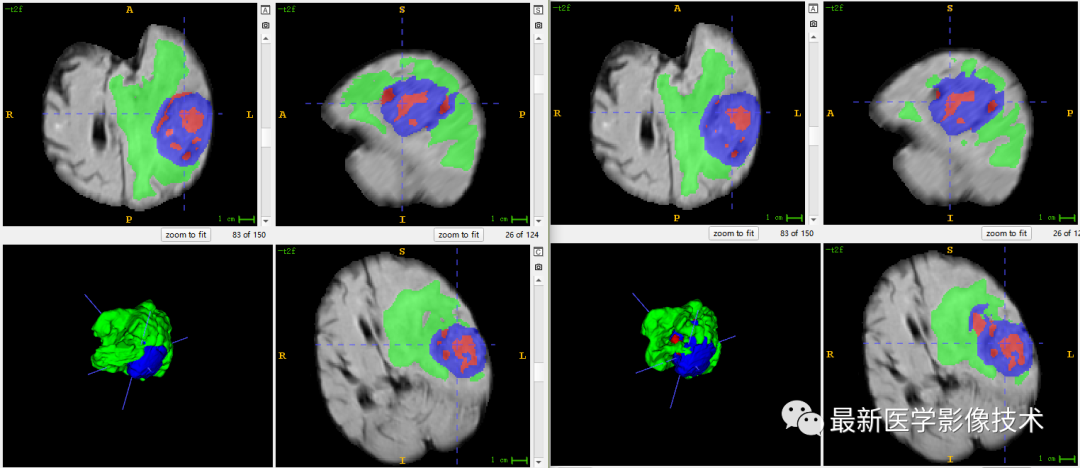

6、验证集分割结果

左图是金标准结果,右图是网络预测结果。